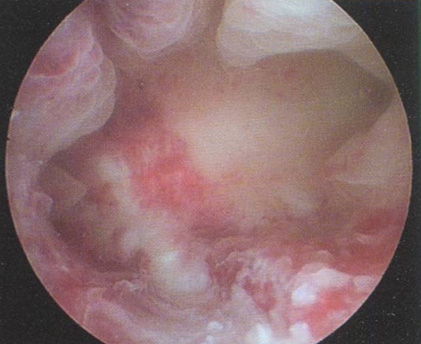

Рис. 3.3. Заключение гистероскопии: гиперплазия эндометрия. Гистологическое исследование: простая железистая ГПЭ.

Гистологическое исследование: простая железистая ГПЭ.